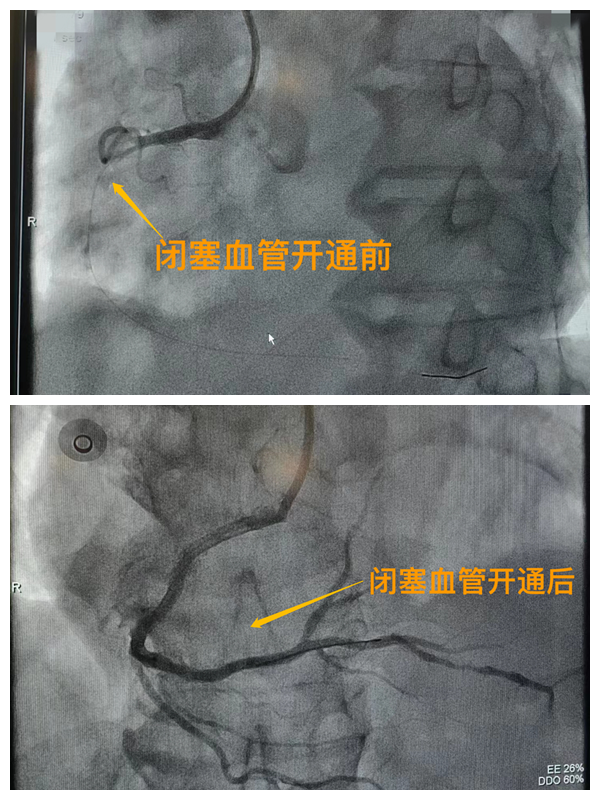

市二院胸痛中心于2021年12月23日通過中國胸痛中心認(rèn)證,成為國家級(jí)胸痛中心,先后開展了冠心病的介入診療、心律失常的心內(nèi)電生理檢查及射頻消融治療、永久起搏器植入、先天性心臟病的介入封堵及臨時(shí)起搏器植入、主動(dòng)脈內(nèi)球囊反搏治療等,完成心臟介入手術(shù)3000余例。多次創(chuàng)造從入院至行急診介入手術(shù)開通血管(入門-導(dǎo)絲通過)30分鐘以內(nèi)記錄,極大保證了患者的生命安全,提高了預(yù)后質(zhì)量,挽救了眾多急性心?;颊叩纳?。(尹紅婭       張   靜)